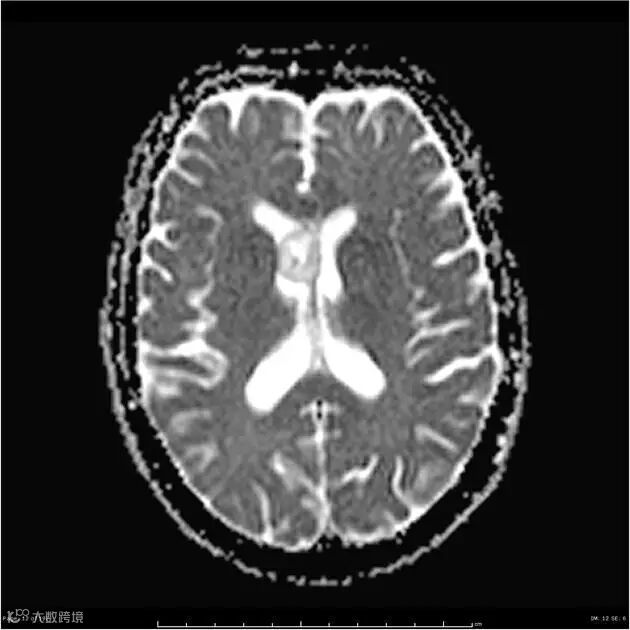

DWI